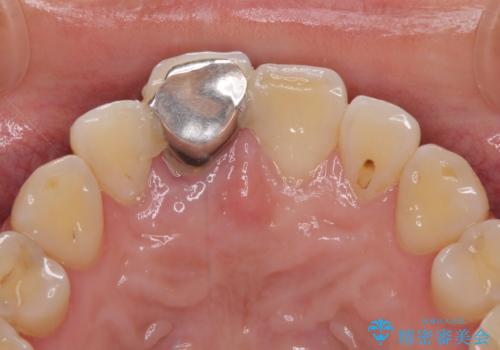

- 歯根が破折しているにもかかわらず、抜歯を避けてきたため痛みが発現したとのことで来院された患者様です。

歯根破折した歯は抜歯適用となるため、速やかに抜歯を行い、傷が治り次第オールセラミックブリッジにて補綴治療を行うこととしました。